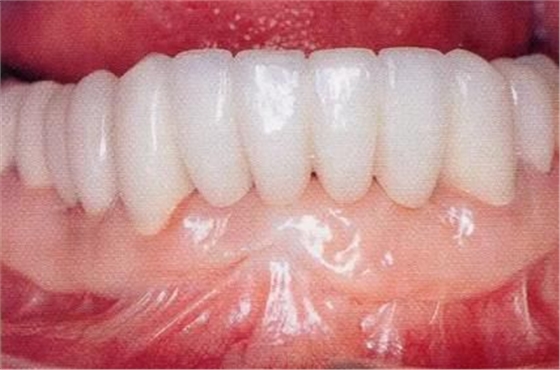

圖16-10 佩戴最終修復(fù)體時。